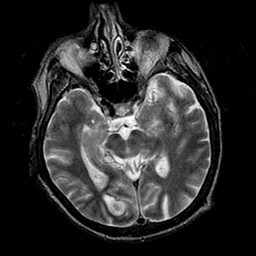

อาศัยการซักประวัติ ตรวจร่างกายทั่วไปและการตรวจทางทางระบบประสาท และการทำเอ็กซเรย์คอมพิวเตอร์ (CT scan) ในบางรายหากสงสัยว่าอาจเป็นอย่างอื่น แพทย์ที่ตรวจอาจให้ตรวจสมองด้วยคลื่นแม่เหล็กไฟฟ้า(MRI) แทนการตรวจเอ็กซเรย์คอมพิวเตอร์

การทำ CT scan ของสมอง จะช่วยให้แยกได้ระหว่างเส้นเลือดตีบหรือแตก ซึ่งการรักษาจะต่างกันไป